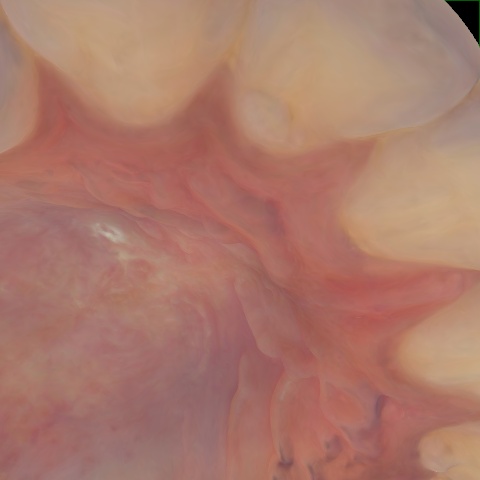

NHD29443

Annotated as "Good"

Original Image Rendering Image